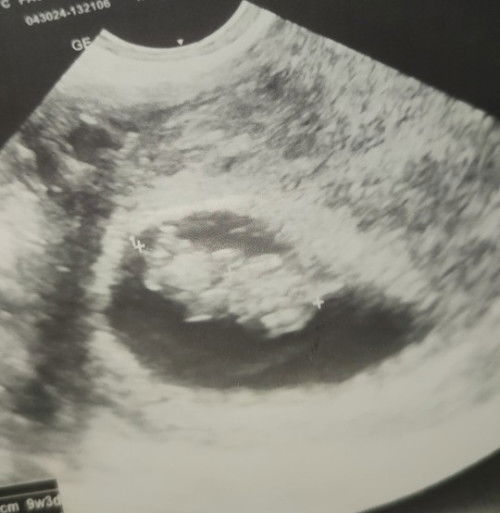

Gender Reveal (?)

hi mga mommies! nagpaultrasound ako last april 30 and that time 9 weeks and 3 days palang ako that time pero feeling ko nakikita ko na agad gender ni baby dahil sa position niyang nakaharap hehe. ano kaya sa tingin niyo? excited lang ako agad malaman haha #firsttimemom #13weeks